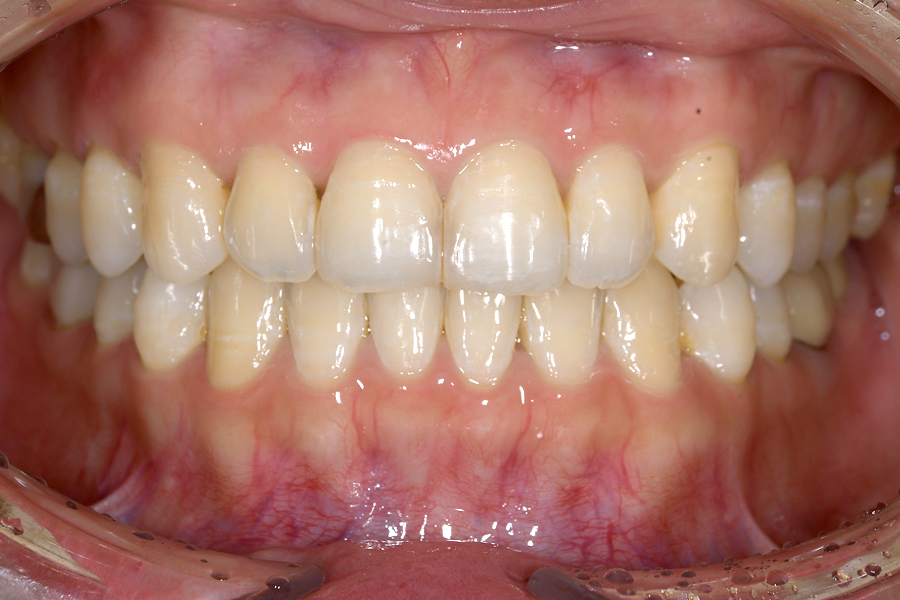

| 主訴 | 歯並びを治したい |

|---|---|

| 治療期間 | 1年9か月 |

| 治療費 | ¥1,023,800(税込) |

| 治療内容 | 目立ちにくいマウスピース矯正(非抜歯矯正) 歯と歯の間に隙間をつくることにより、 歯列弓を広げながら治療を行いました。 |

| 治療のリスク | ・後戻りする可能性があるので リテーナーを最低でも矯正期間以上はつけること ・歯の移動中に、歯の神経が過敏になり冷たいものや熱いものがしみたりする場合があります。 |